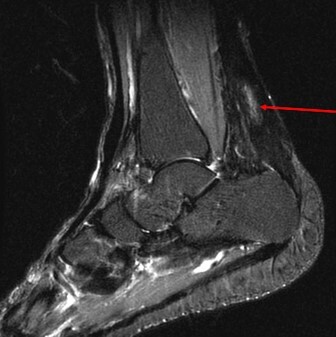

what do see here in this previously damaged achilles tendon

heterotopic calcification